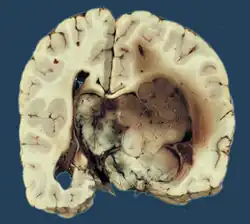

Choroid plexus papilloma, also known as papilloma of the choroid plexus, is a rare benign neuroepithelial intraventricular WHO grade I lesion found in the choroid plexus.[1] It leads to increased cerebrospinal fluid production, thus causing increased intracranial pressure and hydrocephalus.[2]

Choroid plexus papilloma occurs in the lateral ventricles of children and in the fourth ventricle of adults. This is unlike most other pediatric tumors and adult tumors, in which the locations of the tumors is reversed. In children, brain tumors are usually found in the infratentorial region and in adults, brain tumors are usually found in the supratentorial space. The relationship is reversed for choroid plexus papillomas.

Choroid plexus tumors are divided into three categories by the World Health Organization (2016):[9] papillomas (grade I), atypical tumors (grade II), and carcinomas (grade III). Less than two mitotic figures per 10 high power fields are present in CPPs, two to five are present in atypical ones, and more than five are present in carcinomas. The tumors are visible as pink, soft, spherical lumps with erratic projections and considerable vascularity.

A neurosonogram via the anterior fontanelle will show an echogenic lesion inside the ventricles if the fontanelles are not united. This lesion exhibits bidirectional flow throughout the diastole, demonstrating blood flow via disorganized vascular arrangement. Sometimes ultrasound scans are used to diagnose the lesions before birth.[15] An isodense or slightly hyperdense lesion inside the ventricles, as well as the resulting ventriculomegaly, are visible on computer tomography (CT).[16] The intraventricular lobulated masses are well-defined and resemble fronds; they are hypointense on T1WI and hyperintense on T2WI on magnetic resonance imaging (MRI).[17] Active blood flow is indicated by the presence of flow voids. A rich vascularity gives the lesions a brilliant enhancing quality. Recent researches have shown that choroid plexus papilloma and choroid plexus cancer may be distinguished from one another using arterial spin labeling.[18]